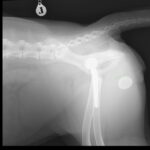

若齢のゴールデン・レトリーバーの股関節形成不全(CHD)に対し、人工股関節全置換術(THR)を実施しました。術前のエックス線では、両側に顕著な股関節亜脱臼を認めましたが、重度の変形性関節症は認められていません。亜脱臼が顕著であることから関節温存のための3Dhip/DPO/TPOは不適応と判断しました。

術後X線評価ではインプラント設置は良好。

カップは寛骨臼内側壁に適切に接触し、前後柱間で良好に中心化されています。

ステムは髄腔中央に位置し、内側皮質との接触も良好です。インターロッキングスクリュー固定も適切で、安定した初期固定強度が得られています。

Angle of Lateral Opening (ALO):約45°

Retroversion:約30°

True stem anteversion:約25°